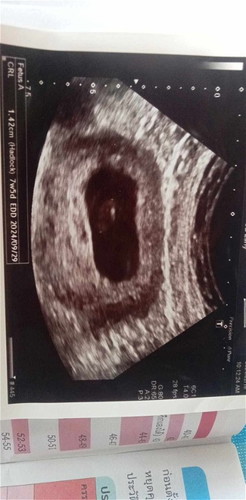

คุณหมอบอกว่าเราตั้งครรภ์ได้ 11 สัปดาห์แล้วเมื่อวานไปอัลตร้าซาวด์คุณหมอบอกว่าไม่พบการเต้นของหัวใจน้องอาจจะเสียชีวิตในครรภ์เป็นไปได้ไหมคะว่าเราอาจจะฝากครรภ์ไวไปแล้วน้องตัวเล็กเกินไปเลยไม่เห็นหัวใจของน้องคุณแม่ใจไม่ดีมากเลยค่ะตอนนี้กลัวจะเสียลูกไปไม่คิดว่าจะเกิดขึ้นกับตัวเอง แต่ไม่มีอาการใดๆเลยไม่ปวดท้องไม่มีเลือดไหลออกจากช่องคลอดตามที่คุณหมอให้สังเกตอาการของตัวเอง ไม่อยากให้เป็นอย่างนั้นเลยเป็นไปได้ไหมคะที่น้องจะตัวเล็กเกินไปเลยไม่มีการตุ๊บเต้นของหัวใจ😭😭😭😭🥺🤦 #แต่ในเครื่องอัลตร้าซาวด์วันที่ไปอัลตร้าซาวด์เครื่องอัลตร้าซาวด์เขียนว่า 7 week 5 day อาจจะเป็นไปได้ไหมคะที่น้องยังไม่ได้ 2 เดือนแล้วเล็กเกินไป